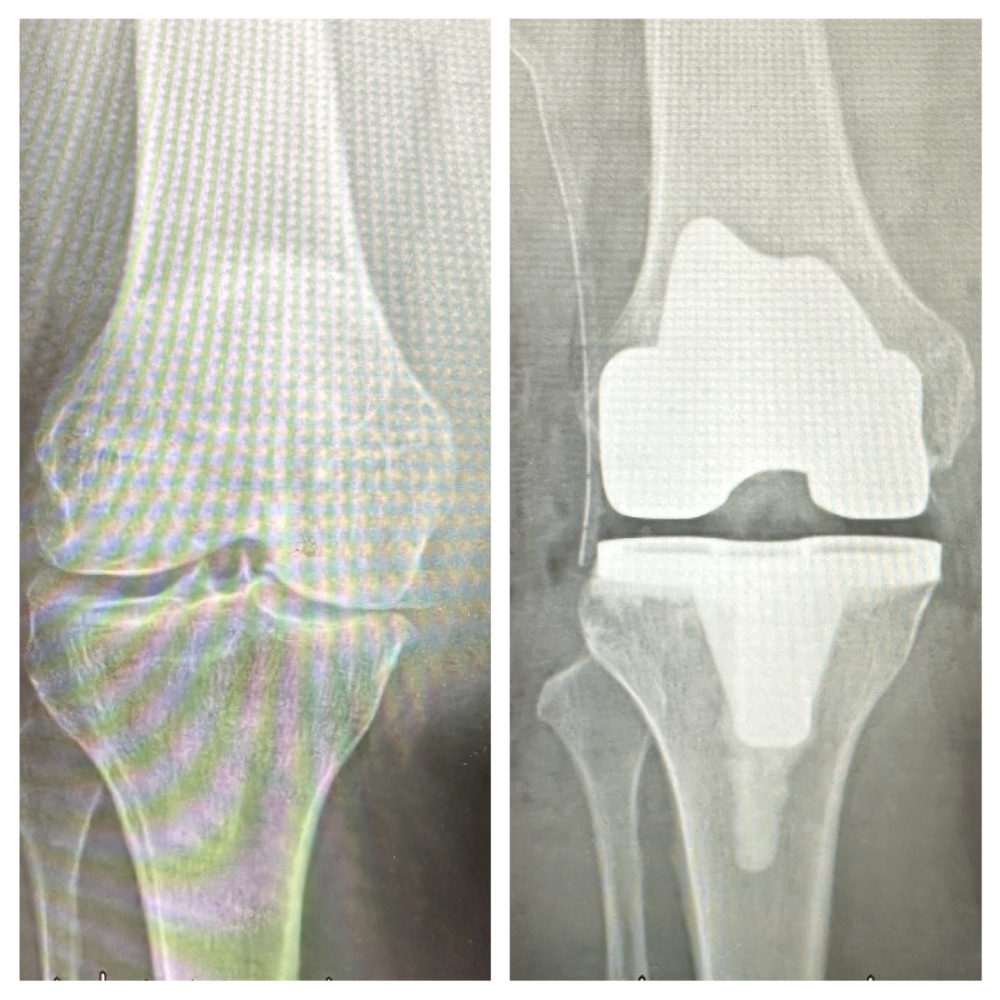

在高齡與慢性病風險交織的情況下,衛生福利部豐原醫院導入「術後加速康復(ERAS)」系統化整合照護模式,讓手術風險得以精準評估並有效控管,最終梁奶奶順利完成膝關節「人工關節置換手術」,術後恢復穩定,疼痛明顯改善,短時間內即可重新站立並開始行走,順利返家休養。

豐原醫院骨科主任呂文憲表示,ERAS照護流程是透過完整風險盤點與流程管理,逐一拆解高齡手術可能面臨的挑戰,此照護模式強調從術前、術中到術後的全期整合照護:術前完成麻醉風險評估、營養調整與用藥規劃。

手術過程中降低生理負擔並精準控制疼痛,減少對身體的衝擊。術後由復健與護理團隊及早介入,設定安全的復原節奏,協助病人下床活動,逐步恢復行走能力,在跨團隊合作下,讓高齡及多重共病患者也能在穩定、安全的條件下完成手術與復原。